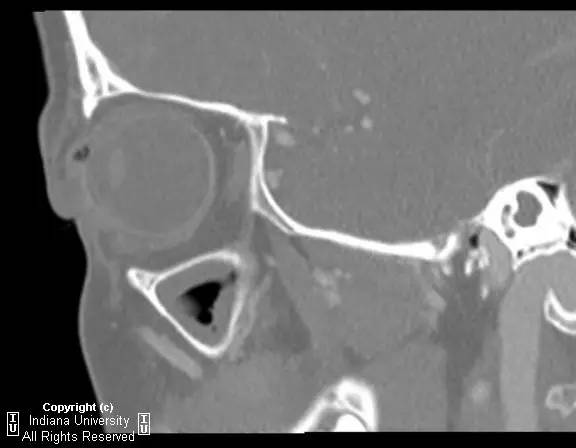

右侧上眼睑软组织肿胀。上眼睑与眼球间可见矩形积气,约1 cmx 0.4 cm x 0.4 cm,并线样影在内穿行。眼球及晶状体正常。眶隔后及眶内软组织无肿胀、血肿或脂肪条纹提示为创伤性。无对比剂外渗。无对急性骨异常。右侧上颌窦粘膜增厚。

【诊断】右上眼睑和眼球间木片存留

There is a piece ofwood between the superior right eyelid and the globe.